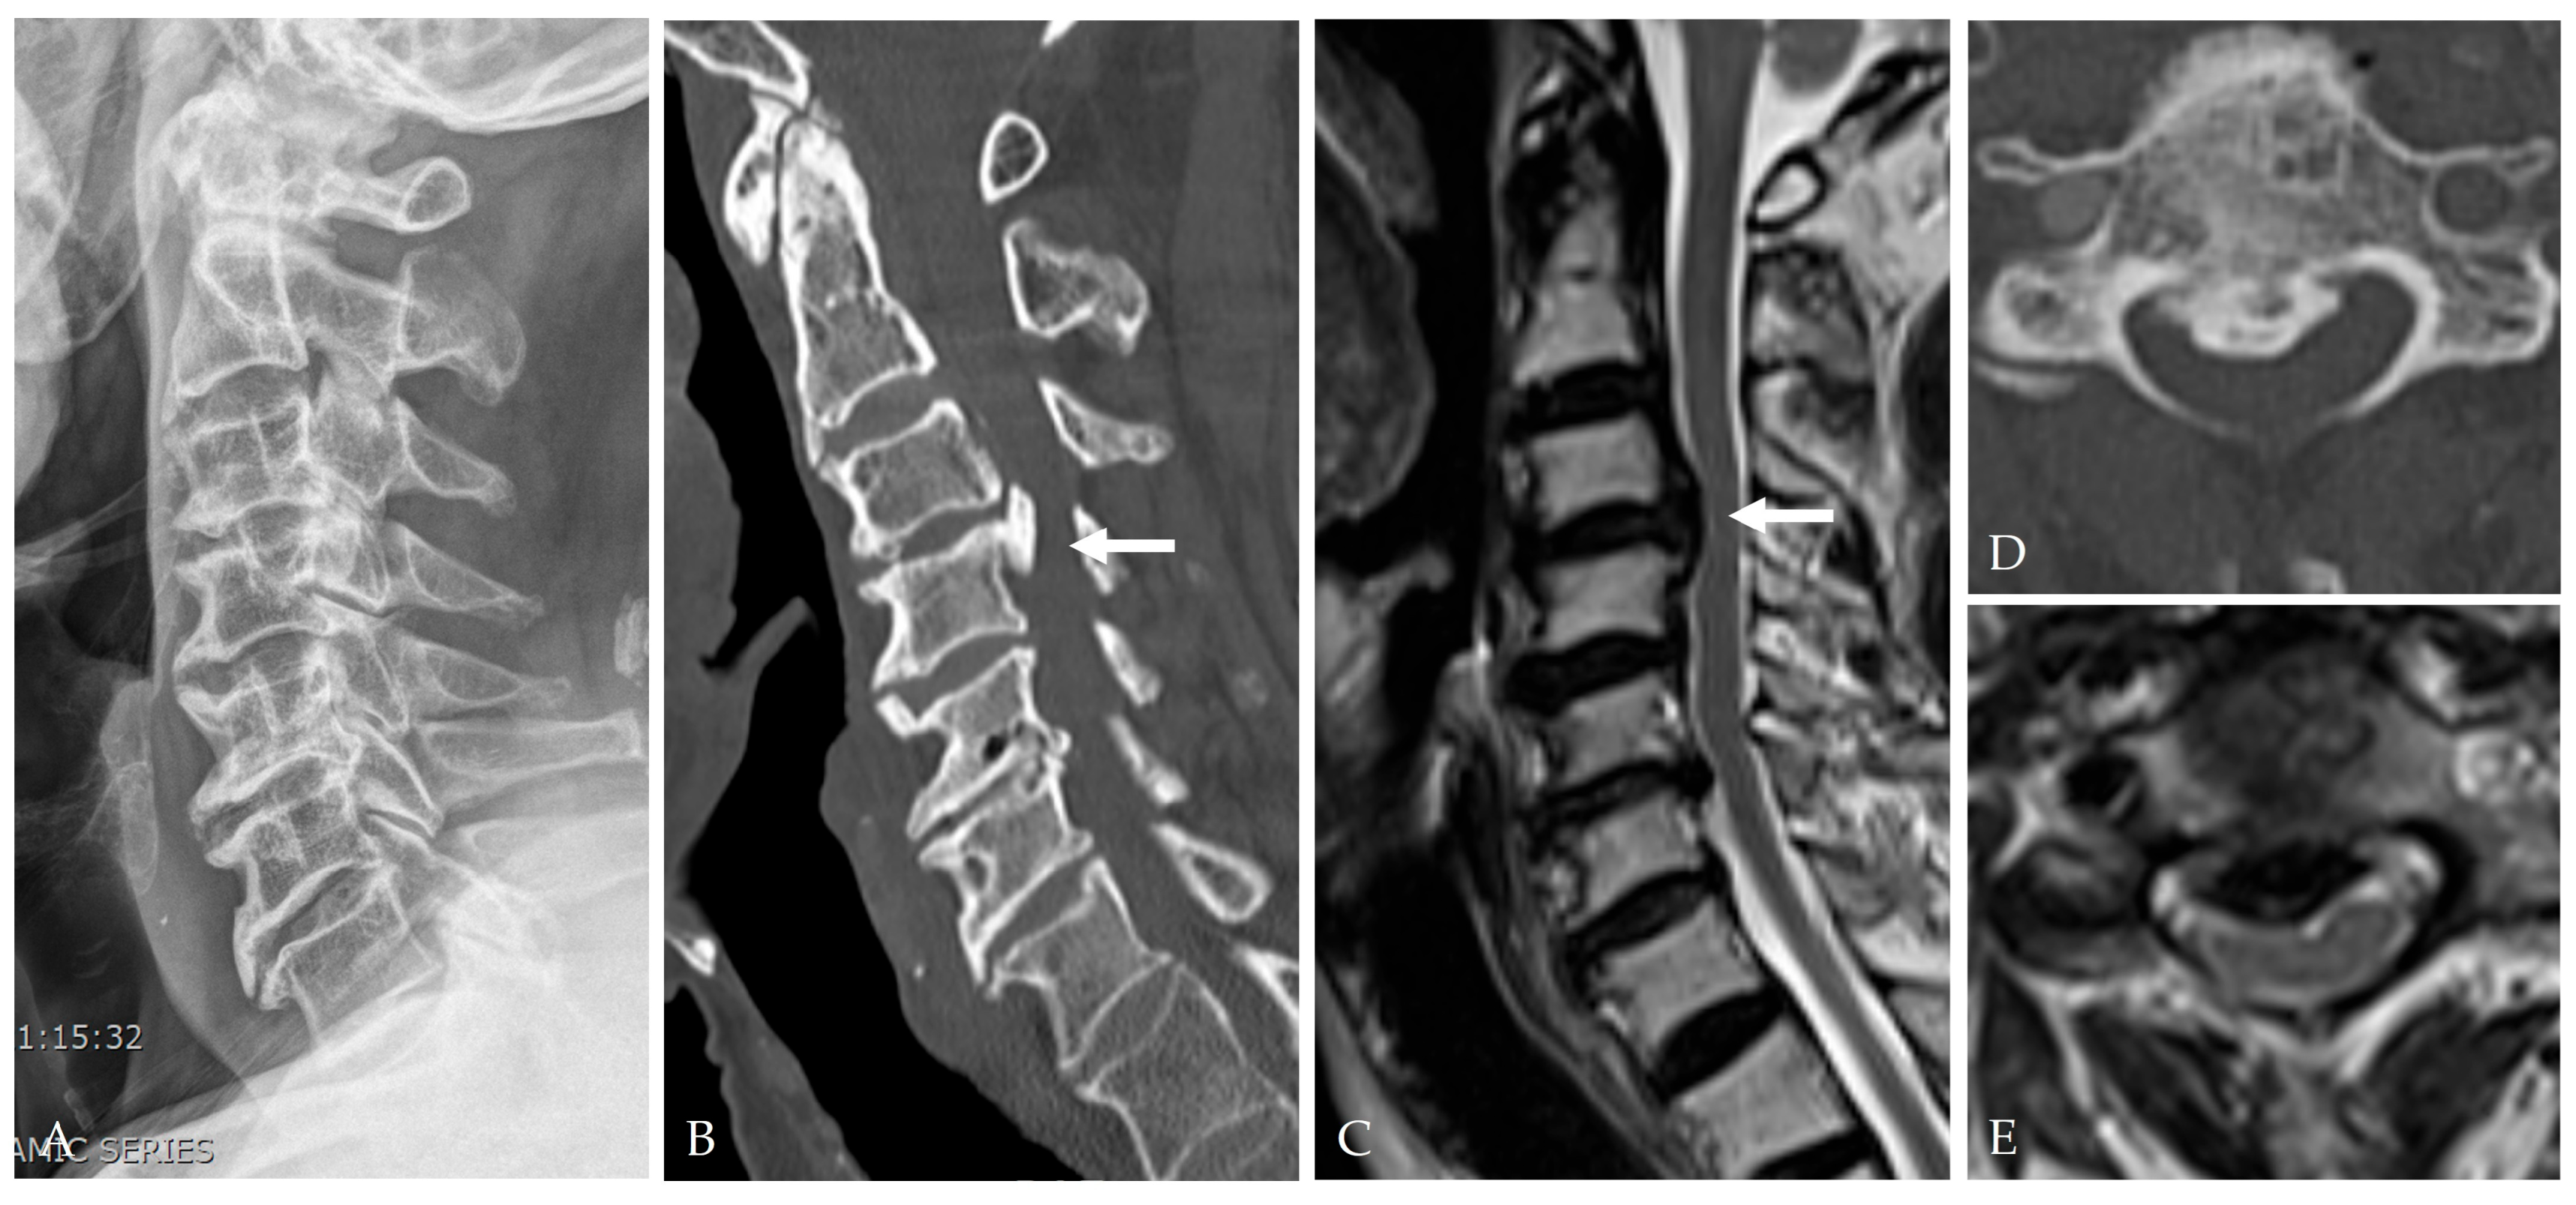

2.4. Radiologic Predictors and Morphological Correlates

- Broad-based or continuous/mixed-type OPLL: Confers approximately 10-fold higher risk of DT than segmental types [37].

2.5. Disease-Specific Factors: Dural Ossification and Adhesion Severity

- Min, J.H.; Jang, J.S.; Lee, S.H. Clinical significance of the double-layer sign on computed tomography in OPLL. Neurosurgery 2007, 61, 118–121. [Google Scholar] [CrossRef]

- Yang, H.; Yang, L.; Chen, D.; Wang, X.; Lu, X.; Yuan, W. Implications of different patterns of the “double-layer sign” in cervical OPLL. Eur. Spine J. 2015, 24, 1631–1639. [Google Scholar] [CrossRef]

- Chen, Y.; Guo, Y.; Chen, D.; Lu, X.; Wang, X.; Tian, H.; Yuan, W. Diagnosis and surgery of OPLL associated with dural ossification in the cervical spine. Eur. Spine J. 2009, 18, 1541–1547. [Google Scholar] [CrossRef]

- Epstein, N.E. Identification of OPLL extending through the dura on preoperative CT of the cervical spine. Spine 2002, 27, 182–186. [Google Scholar]

- Mizuno, J. Radiologic evaluation of ossification of the posterior longitudinal ligament with dural ossification. Neurosurg. Clin. N. Am. 2018, 29, 55–61. [Google Scholar] [CrossRef] [PubMed]

- Du, Y.Q.; Cui, G.Q.; Qi, M.Y.; Zhang, B.Y.; Guan, J.; Jian, F.Z.; Duan, W.R.; Chen, Z. A novel CT scoring system for evaluating dural defect risk in anterior OPLL surgery. Clin. Neurol. Neurosurg. 2024, 242, 108315. [Google Scholar] [CrossRef]